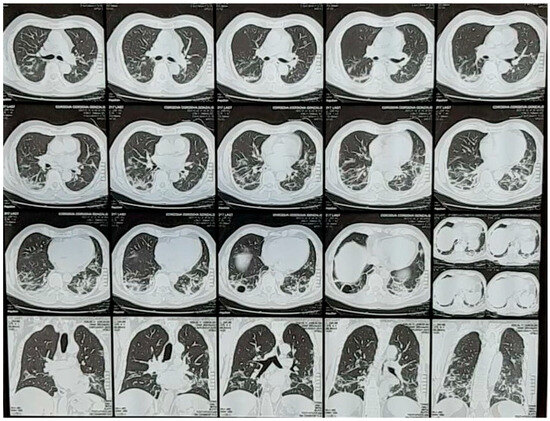

In 2019, the COVID-19 CAT scan compromise presented a distinct pathology (Figure 1). Some authors noted that it was different but did not fully understand it and suggested autopsies be performed [7]. Several autopsy studies of COVID-19 show fibrotic, bullae-filled, necrotic lung tissue, clearly distinct from SARS-CoV-1, which is more hemorrhagic (personal communication by Paolo Pelosi). Others reported diffuse alveolar damage (DAD) [14], chronic lung inflammation, and edema in the bronchial mucosa, with some finding thromboembolic events [15,16].

Figure 1.

CT scan of a typical patient with COVID-19 lung disease. Courtesy of Centro de Estudios Tomográficos (CET) La Paz, Bolivia. Pneumolysis can be so severe that even bullae can be formed (3rd row, middle frame).

COVID-19 is a fast-track production of emphysema-type lesions, as it destroys alveoli without time for remodeling and adaptation. It creates bullae (Figure 1) and small cavities similar to those seen in TB. These bullae were also present in previous biopsies [31]. Mycobacterium tuberculosis proliferates inside alveolar macrophages and eventually kills the cells [32]. The tuberculosis attack is intracellular, making treatment difficult and requiring long-term therapy for up to a year. The infected macrophages produce cytokines and chemokines that attract other phagocytic cells, including monocytes, other alveolar macrophages, and neutrophils, which eventually form a nodular granulomatous structure called the tubercle [33]. However, this takes quite a bit of time. In COVID-19, there is no time, as the intracellular coronavirus bio-attack is fast. The same phagocytic cells are, however, present in COVID-19, as described below. Adaptation to survival within the disease takes time. The high-altitude adaptation formula shows a typical hematopoietic time frame in response to ascent to a fixed high altitude [34], which requires 40 days for an optimal increase in hematocrit at 3600 m (12,000 ft.).